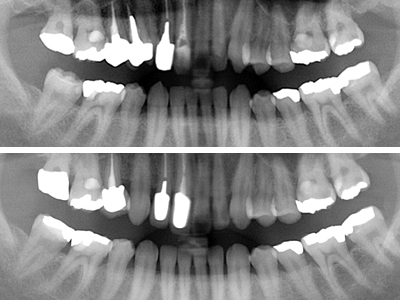

全顎パノラマ写真においては右上1番が失活歯、2番は叢生のままで不適合な前装冠(差し歯)、八重歯の3番は健全歯、4,5番も2番同様不適合冠処置となっています。比較的プラークコントロール(以下PCR)の良好な(歯ブラシの仕方が上手な)この患者様も同部が上手に磨けず不潔となり崩壊過程にあることが考えられます。

18. 術後X線写真

初診時X線パノラマ写真と比較してレントゲン上でもシンプルだと考えます。4番の近心側のPCR等は注意して、今後の定期健診に期待いたします。